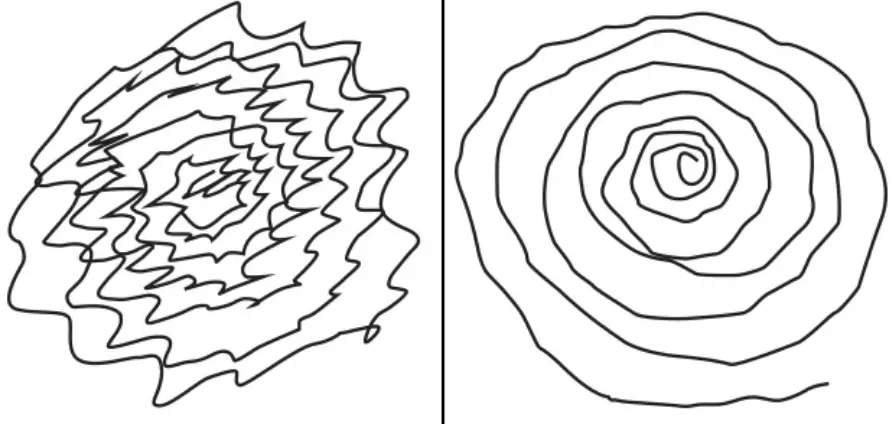

- Escrita pequena e apertada

O tremor essencial é o tipo mais comum de tremor que existe. Ele costuma afetar as mãos, mas também pode atingir a cabeça, a voz ou outras partes do corpo.

Diferente do tremor do Parkinson, que aparece quando a pessoa está parada, o tremor essencial surge quando você está fazendo algum movimento, como:

- Beber água

- Escrever

- Comer com talheres

- Passar maquiagem ou fazer a barba